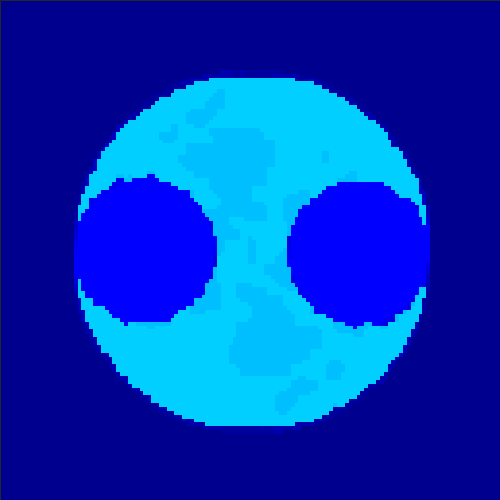

5.2 Monte Carlo Simulation

In order to test the behaviour of the proposed method in a more realistic, random-based test case, we performed a Monte Carlo simulation for dynamic SPECT imaging. First, we created a simple image phantom consisting of an outer and two inner circles which represents the structure of the region of interest (see figure 8(a)). Within those regions we assumed concentration curves over a time period of 90 time steps as displayed in figure 8(b). Based on the tracer intensity in an image frame at each time step, we created a variable number of random decay events (where the number is proportional to the average concentration in one pixel in the whole image frame per time step) with a probability proportional to the concentration in every subregion. They are detected by a virtual double head gamma camera rotating around the patient by 46 degrees per time step, which consists of 374 detector bins. Every simulated decay event is projected onto the scanner and counted by the corresponding detector bin.

In two different tests we fixed the number of events counted by the detector equal to (resp. ) times the average concentration in one pixel. The resulting sinogram images of the accumulated counts in each bin are shown in figure 9.

Based on the sinogram data we applied the proposed algorithm in order to reconstruct the original image sequence. The results for both test cases are shown in figure 10.

As one can see, the method is able to reconstruct the regions properly, even in case of a low count number. Within a number of iterations (average of 100 outer and 10000 inner iterations), the algorithm presents a reasonable reconstruction of the region of interest and the corresponding regional tracer concentration curves. Here, the parameters were not optimized as in the case of the synthesized data sets in the previous section, but kept fixed as , and . With futher optimized parameter values one could possibly provide even better results.